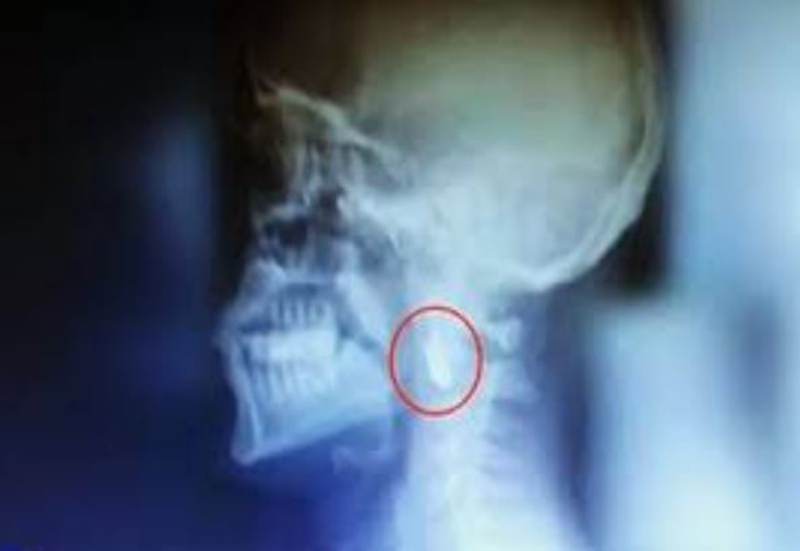

Darbeci hainlerin karşısına dikilen Gazi İsmail Acur, kurşunların hedefi oldu. Acur, 8 yıldır boynunda kurşunla yaşıyor. Kurşun, şah damarı ile omurilik arasında olduğu için cerrahi müdahale yapılamıyor.